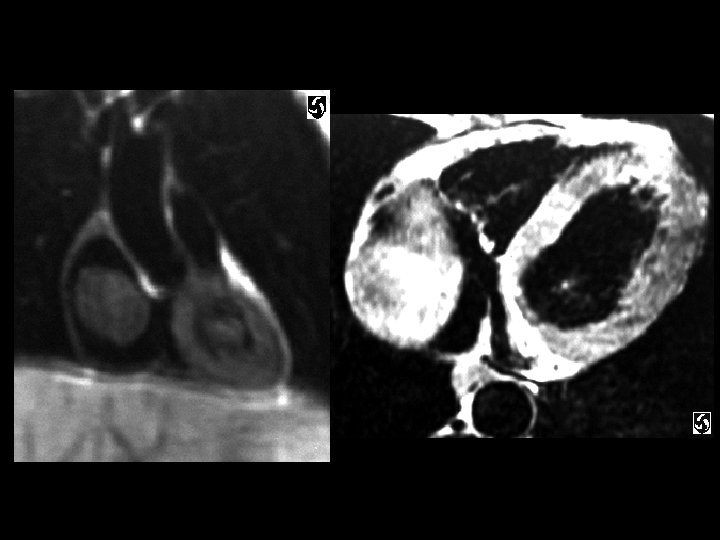

Rhabdomyoma • Findings: – right atrial mass with partial obstruction of the inferior vena cava • ddx: – myxoma – lipoma – angiosarcoma